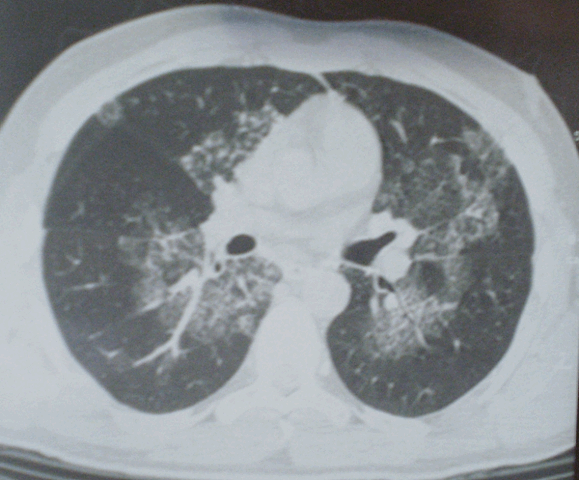

Компьютерная томография органов грудной полости: на серии компьютерных томограмм получены изображения легких и средостения в аксиальной плоскости на уровне вдоха по стандартному протоколу. Легкие обычных размеров и формы, с дополнительной долей непарной вены в правом легком. Легочный рисунок резко деформирован по мелко- и среднепетлистому типу в прикорневых отделах с обеих сторон. Также отмечаются участки и зоны деформации легочного рисунка по мелко- и среднепетлистому типу и по типу «матового стекла» в плащевых отделах легких с обеих сторон – симптом «географической карты». Во всех отделах определяются множественные плевральные сращения. Корни легких структурны, с наличием множественных бронхопульмональных лимфатических узлов (0,2-0,5 см в диаметре) в структуре. Стенки трахеи и бронхов умеренно уплотнены, с наличием мелких бронхоэктазов в задне-базальных отделах слева. Сердце умеренно увеличено в размерах, преимущественно за счет левых отделов. Жидкости в плевральных полостях не обнаружено (рис. 2).

Рисунок 2б. Компьютерная томограмма органов грудной клетки: изменения легочного рисунка по типу «матового стекла». Множественные плевральные сращения

- нетипичная для АП локализация поражения: по данным КТ ОГК отмечается поражение не только задне-базальных, но и верхних отделов легких (рис 2). Помимо этого, визуализируется поражение плевры в виде множественных плевральных сращений, что не характерно для АП.